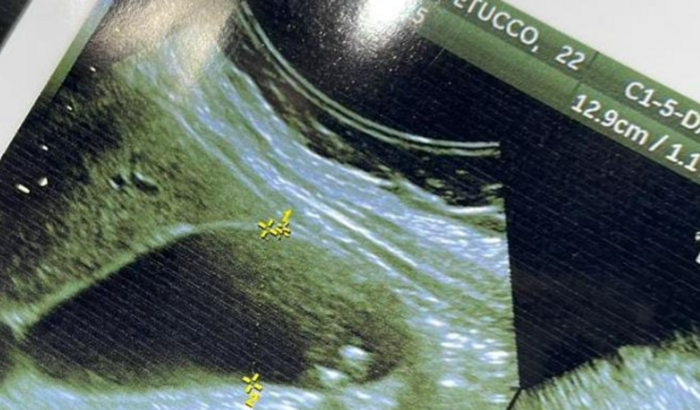

Meu nome é Valquiria e tenho 22 anos. Por conta de dores intensas, descobri que estou com pedras na vesícula, preciso de uma cirurgia urgente, pois as crises de dores estão piorando e a longo prazo isto pode agravar, o que pode me causar pâncreatite, me levando a UTI, corforme o que o médico alertou.